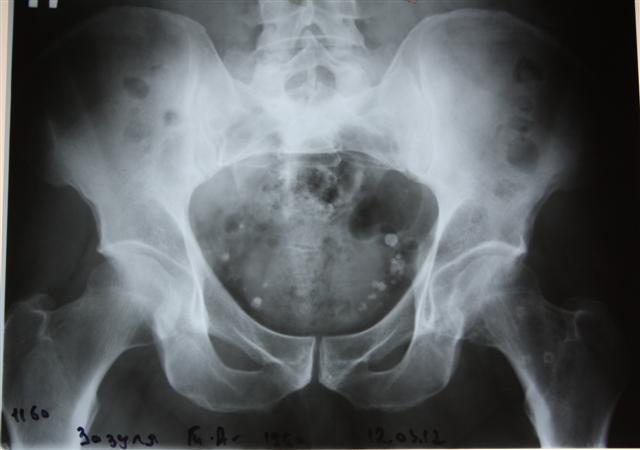

Мы имеем опыт более 100 операций одноэтапного двустороннего эндопротезирования тазобедренных суставов.

На сегодняшний день общепризнано, что эндопротезирование тазобедренного и коленного суставов является единственным эффективным методом лечения при разрушении суставного хряща и позволяет избавит пациента от боли и вернуть его к активной жизни. В мире ежегодно выполняется более полутора миллионов таких операций. Современные эндопротезы служат десятки лет и позволяют жить полноценной жизнью даже молодым и активным пациентам, а в случае, если эндопротез всё же износился, его можно заменить на более сложный и продолжать пользоваться всеми благами жизни.

Ортопедическое отделение Главного военного клинического госпиталя им. акад. Н.Н.Бурденко занимается вопросами эндопротезирования крупных суставов более 30 лет. Мы прошли весь тернистый путь проб и ошибок в освоении этой специальности, познали горечь неудач и радость успеха. В отделении разработаны и запатентованы: уникальная методика двухэтапного эндопротезирования тазобедренных суставов, новые способы костнопластического замещения значительных дефектов вертлужной впадины при ревизионных операциях.